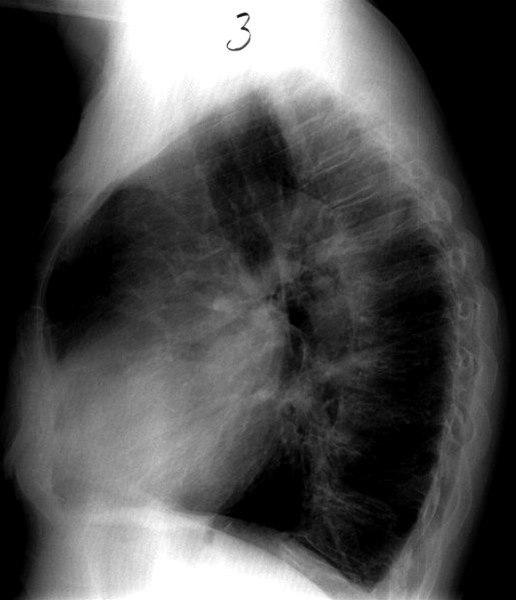

Cor pulmonale - side

Cor pulmonale (hjertestuvning på grunn av stor motstand i lungekretsløpet)

Forstørret høyre hjertehalvdel

Bifunn: Tydelig forkalket aortabue